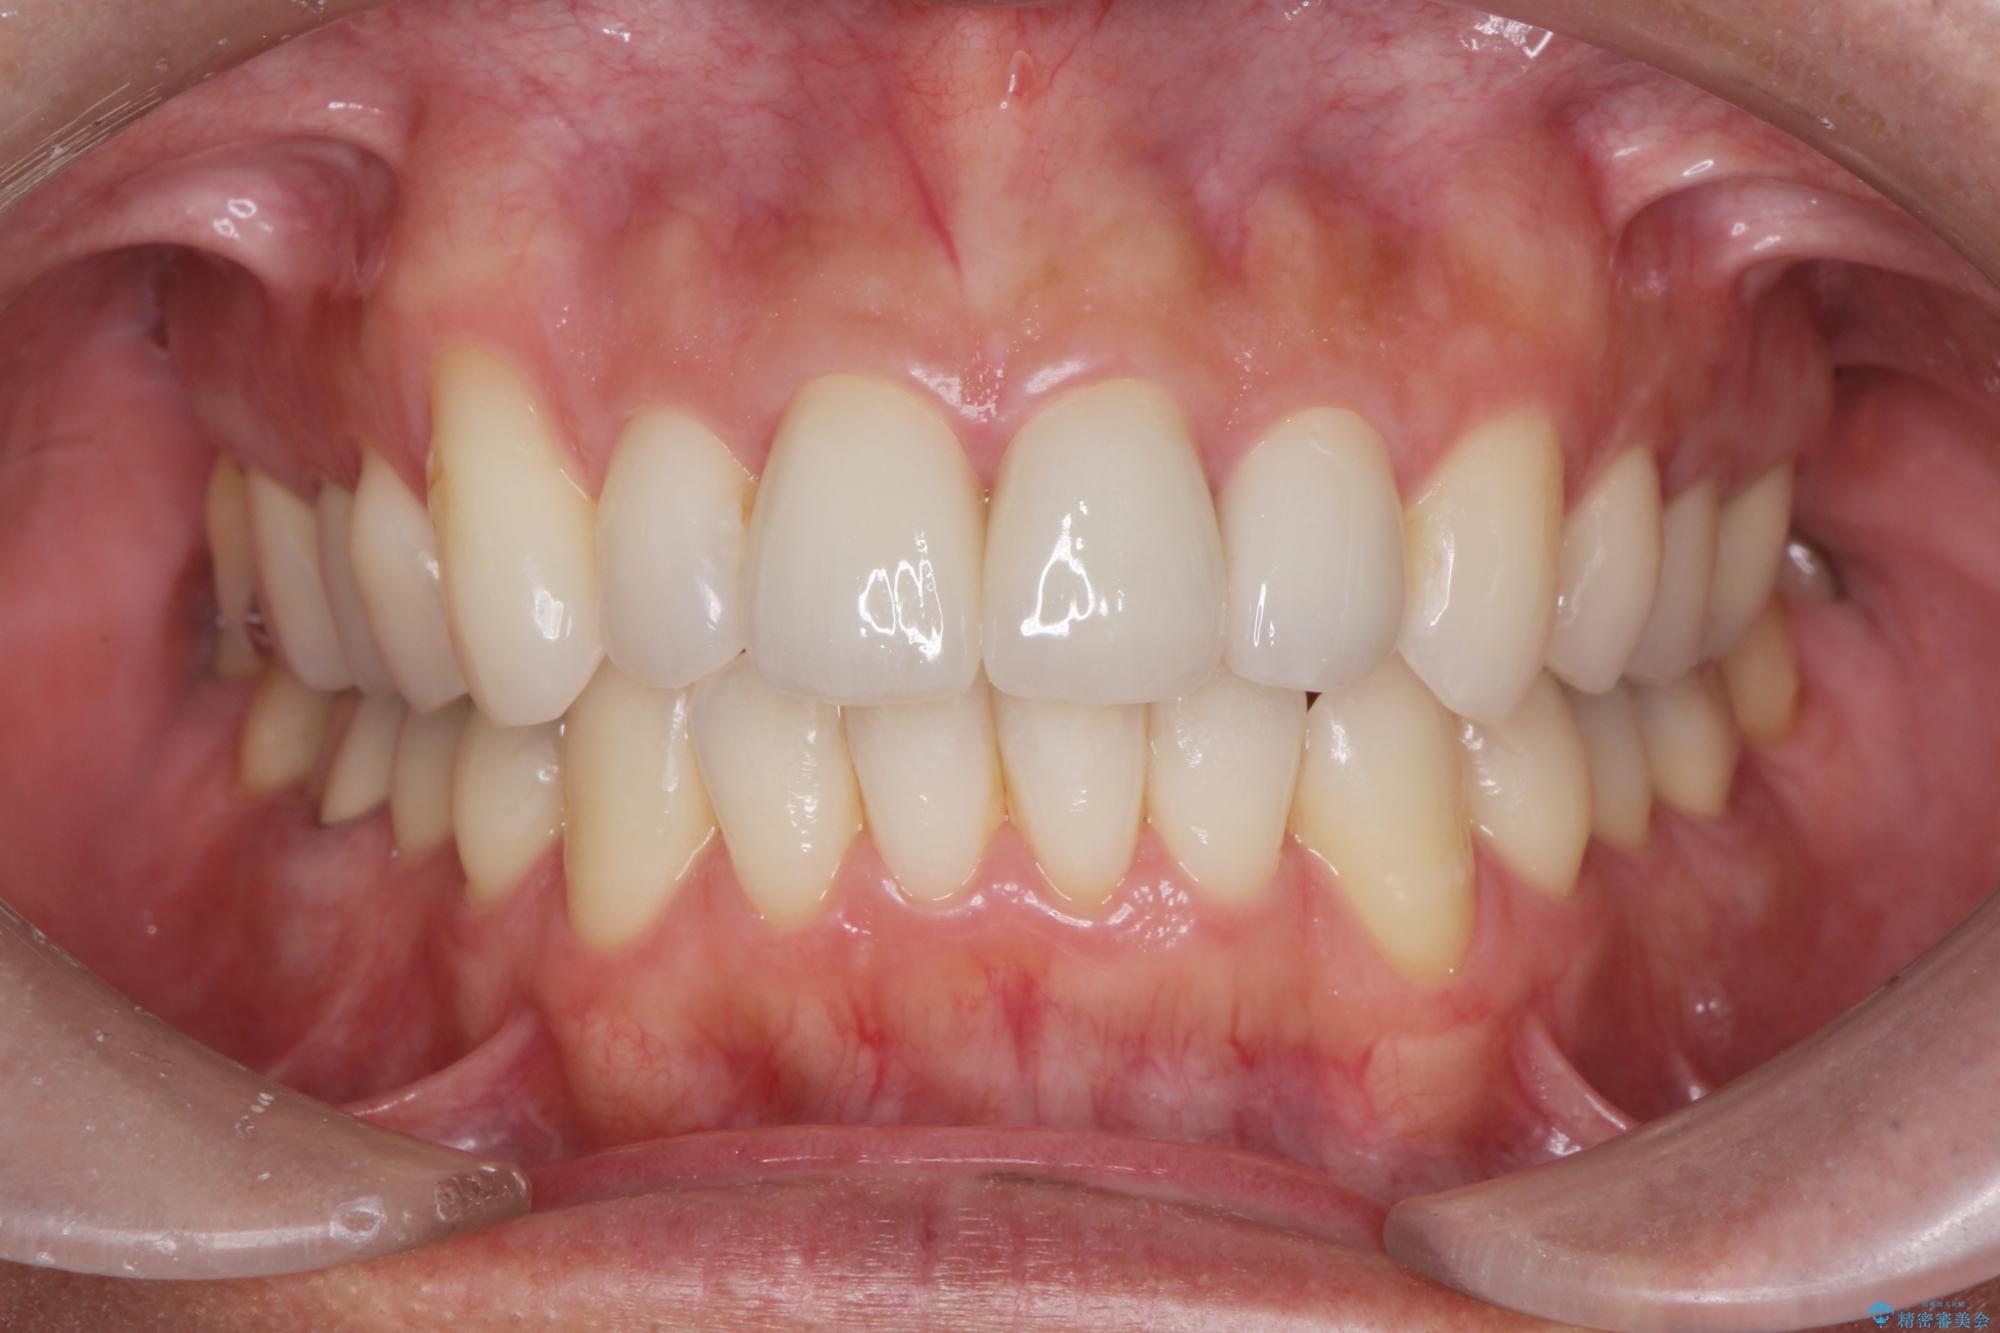

矯正と虫歯のセラミック治療 総合歯科治療の実践

- 突き出た前歯の角度の改善と虫歯治療の改善を求めて来院されました。

虫歯を除去したのち、マウスピース矯正治療を行い、歯並びやがたつきを改善したのち、セラミックに置き換えることで審美性の向上を計画します。

矯正や虫歯治療、セラミック治療といった複合的な治療を一医院で行うことができるのが当法人の大きな特長です。